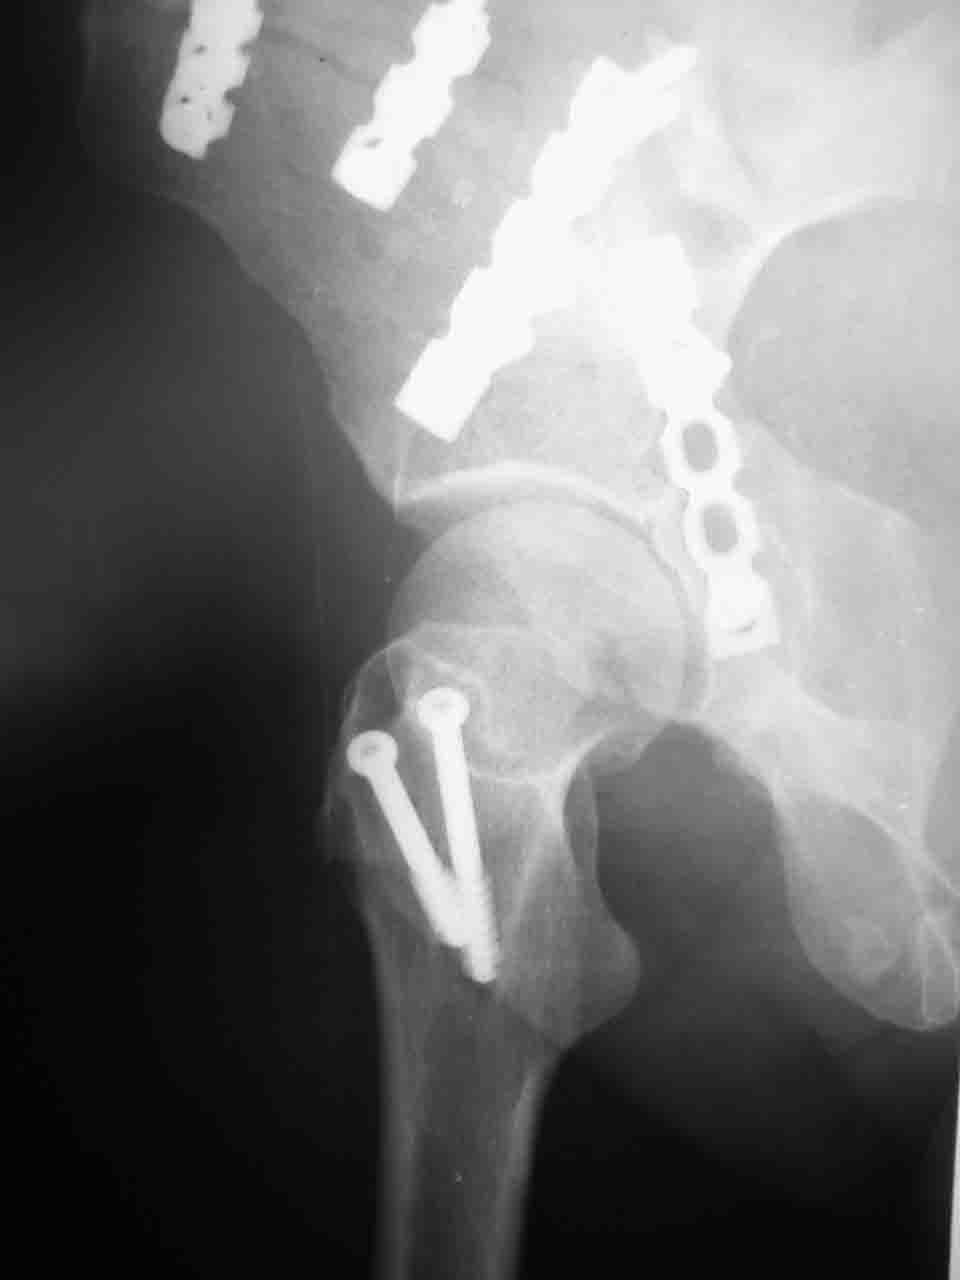

> передним доступом на двухколонный перелом?

Илеофеморальный доступ не совсем передний и сравнительно с илеоингвинальным, и Кохера-Лангенбека открывает весь наружный таз кроме самых передних отделов лонных костей, фиксацию которых я не ставил в задачу. Обширность диссекции, большая длительность операции и более высокий риск гетерооссификации - отрицательные моменты в обмен на возможность легче ориентироваться.

Комбинированные доступы - хорошая альтернатива, меньший процент осложнений, но я заметил , что без сбора *мозаики* безымянной кости сложно отрепонировать переднюю колонну, а с нерепонированной передней колонной невозможно анатомично собрать заднюю колонну и соотв. фрагменты стенки - так.что все равно открывать придется широко. Поэтому выбирая комбинированный

подход, передний доступ должен был бы быть продлен до задней трети крыла безымянной кости, а задний - практически до того же уровня, оставляя 6-7 см мостик. При этом вместо одного послеоп. рубца у больного остаются два сравнительно длинных.

Вопрос доступа к вертлужной впадине при остеосинтезе задача не простая. Конечно, у Летурнеля и Тайла всё давно описано, нам остается только брать на вооружение. Но сами понимаете, что не бывает двух одинаковых ситуаций, поэтому в каждом случае вопрос решается сугубо индивидуально. Наша главная цель - восстановить анатомию с нанесением минимальной дополнительной травмы тазобедреннному суставу, думаю с этим никто не поспорит. Расширенный илиофеморальный доступ уж слишком травматичен (как сказал один коллега "таз лежит отдельно, больной отдельно").Стоит ли делать из пациента анатомический препарат для того чтобы легче ориентироваться. Да и нужно ли собирать всю "мозаику"? Мы применяли при таких операциях своеобразную операционную хитрость - сначала устраняли грубое смещение крыла под гребнем с фиксацией так называемой "плавающей" пластиной (временно фиксированной на двух винтах)- доступ или продлевали боковой, или делали небольшой дополнительный разрез над гребнем. Это позволяло устранить грубое смещение и захождение отломков тела повздошной кости, что значительно облегчало репозицию и остеосинтез впадины над сводом. Основное внимание конечно же уделяли нагружаемому задне-верхнему отделу. Сообщите ваш адрес, пришлю схемы и рентгенограммы.